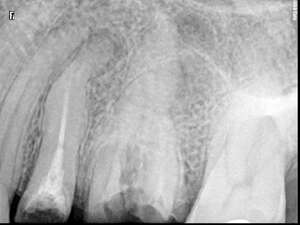

Cas du patient 3

Avant

Après